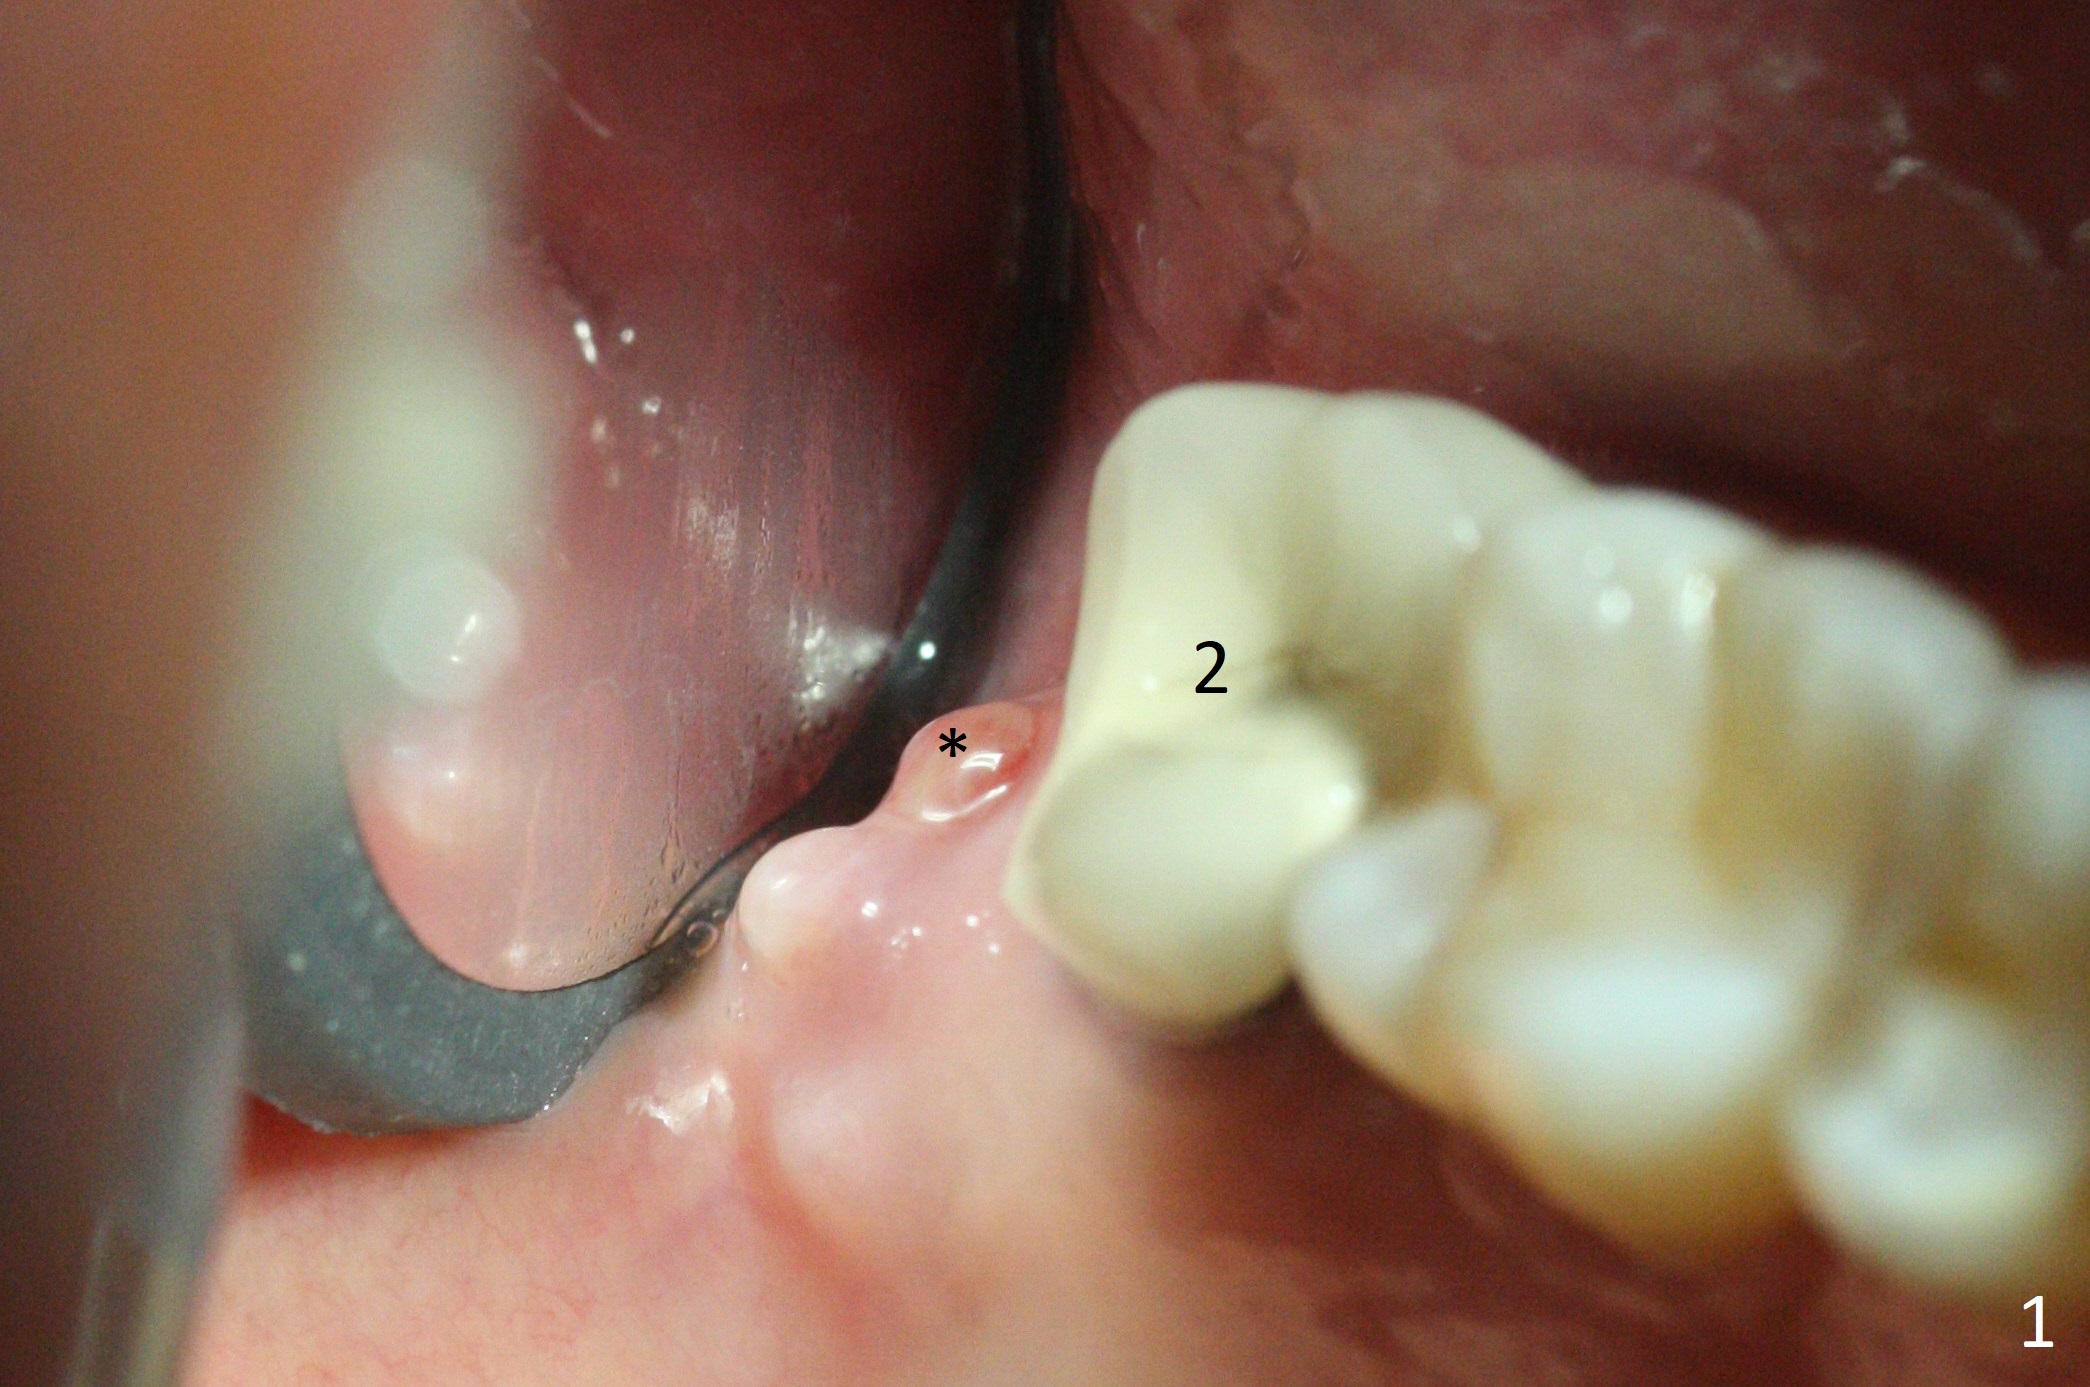

There is a fistula distal to the tooth #2 with deep pocket distopalatally (Fig.1 *), corresponding to palatal root fracture (Fig.2). There is a septum (Fig.3 S) between the buccal (B) and palatal (P) sockets. Osteotomy is initiated in the center of the septum (Fig.4 black circle). In fact the center of the socket is buccal (red circle), in which osteotomy should have been established because of the presence of the distopalatal bony defect associated with the root fracture and the distal fistula. The less ideal initial osteotomy leads to palatal placement of the implant and abutment (Fig.11 vs. 12).